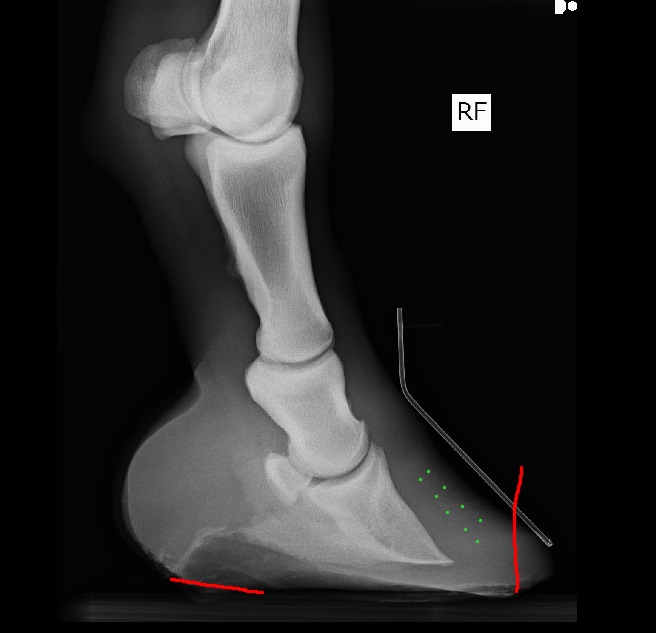

Nutona, вот нарисовала как бы я убирала зацеп.

(зелеными точками обозначила "контур" клина, видно плохо на данных снимках, хорошо бы в программе настройками поиграть, может, станет заметнее)

Зачем убирать зацеп: если представить, что лошадь ходит не по абсолютно ровному твердому грунту, то можно представить, что при опускании копыта в грунт отсутствие верного переката создает "оттягивающее" давление на зацеп, в котором и так уже нарушено соединение. И это даже когда она просто стоит, а когда начинается движение - давление на зацеп будет еще больше при "перекатывании".